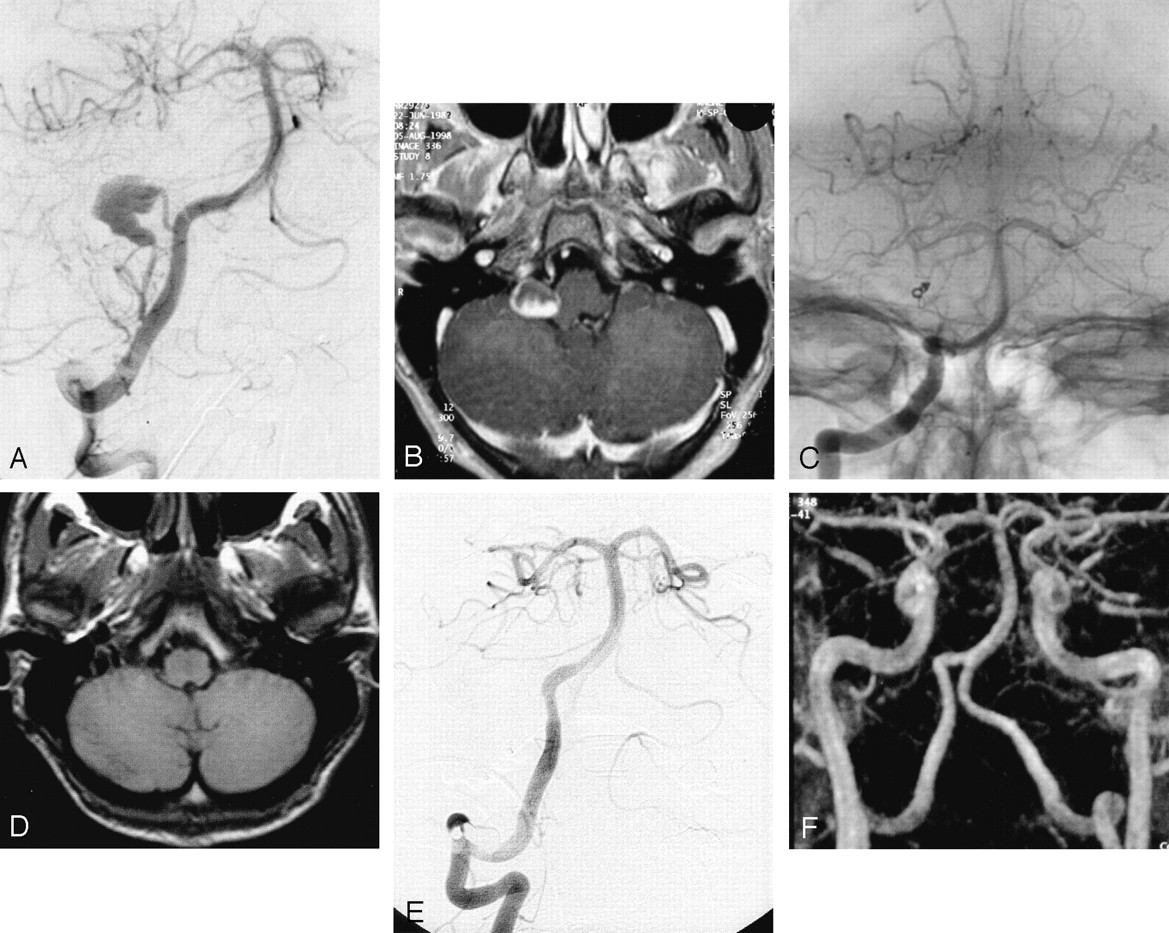

Selective embolization (Fig 1) was performed in five patients who each had a small aneurysm with a small neck. Complete occlusion was achieved in two patients, a neck remnant was present in each of two, and residual flow was observed in one. Parent artery occlusion (Fig 2) performed in large peripheral cerebellar artery aneurysms (two patients) or in a small aneurysm with a wide neck (one patient) led to complete aneurysmal thrombosis.

Subarachnoid hemorrhage (Hunt and Hess grade V) in a 19-year-old male patient.

A, Cerebral angiogram of the left vertebral artery shows distal aneurysm of the left superior cerebellar artery.

B, Selective opacification of the left superior cerebellar artery shows small aneurysm with favorable neck:body ratio.

C, Control angiogram obtained immediately after treatment shows complete aneurysmal occlusion.

D, MR image obtained at 6 months shows residual flow in the central part of the aneurysm without neck opacification.

E, MR angiogram obtained at 6 months shows residual flow in the central part of the aneurysm without neck opacification.

F, Follow-up conventional angiogram obtained at 12 months shows unchanged residual flow.

G, Follow-up MR angiogram obtained at 36 months shows unchanged residual flow.

Follow-up conventional angiograms and MR angiograms were obtained for all patients. Mean duration of follow-up was 18.5 months. MR imaging and MR angiography performed at 6 months after treatment were in accordance with the results of the conventional angiography performed at 12 months. All five aneurysms that were completely occluded after endovascular treatment remained unchanged. Control angiography and control MR imaging performed at 1 year for patients with neck remnants shown by postprocedural angiography (two patients) showed further thrombosis with complete occlusion of the malformation (patients 2 and 6). In one patient with a superior cerebellar artery aneurysm and residual flow, the degree of occlusion remained unchanged 36 months after treatment (Fig 1). This patient’s follow-up included MR angiography, and no further treatment was planned. All patients remained clinically unchanged during the follow-up period; one patient (patient 7), therefore, still had VIIth cranial nerve palsy.